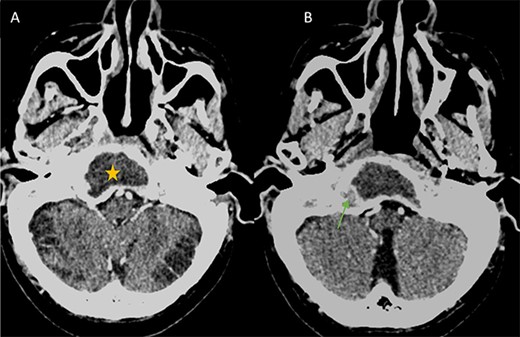

A computed tomography (CT) scan with intravenous contrast was performed (Figs 1 and 2), it revealed:

Bone destruction extending to the petrous, tympanic, and mastoid portions of the temporal bone, with involvement of the body and right greater wing of the sphenoid as well as the occipital bone, and concomitant sequestrum formations within the necrotic bones.

Presence of soft tissue in the middle ear cavity and in the mastoid cells.

Axial CT in bony window showing: (A, B) extensive bone erosion of the clivus and the body and right greater wing of the sphenoid. (C) Soft tissue in the middle ear cavity and mastoid cells.